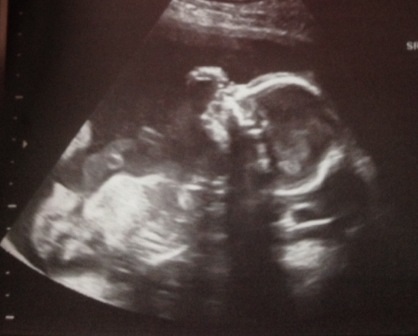

My a/s was traumatic, but all is well now and baby appears healthy. The pic is our 6 year old daughter on the left, and our current baby on the right, Vivienne Rose!

20w - A/S photo from this morning! It's a Girl!!